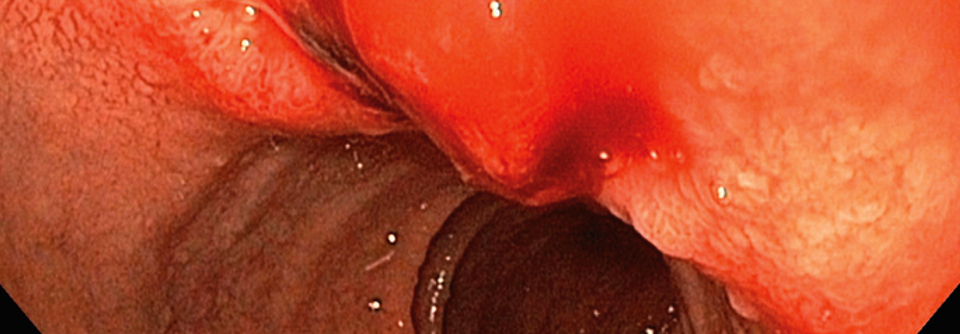

So sieht die Stelle nach der Polypektomie aus. So sieht die Stelle nach der Polypektomie aus. © Immanuel Albertinen Diakonie/endoskopiebilder.de